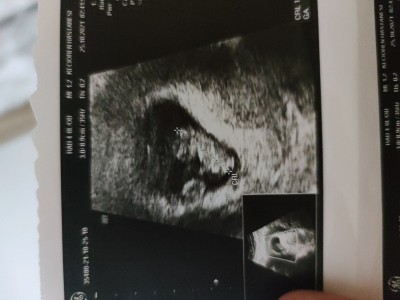

Tek mi çift mi resimli

bebegin yanındaki plesenta mi acaba

Tek canım. İkinci yolk kesesi ve plasenta.